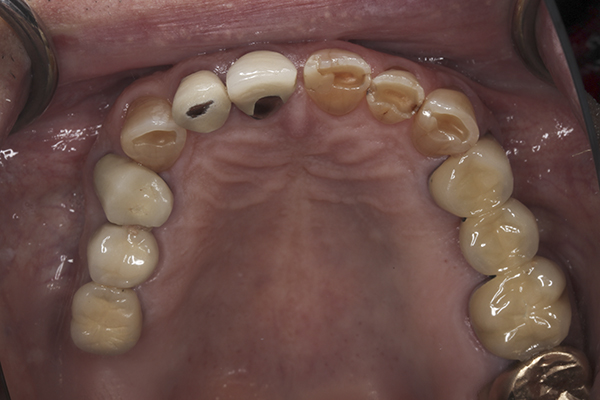

(15.) Preoperative maxillary, occlusal view.

Figure 15